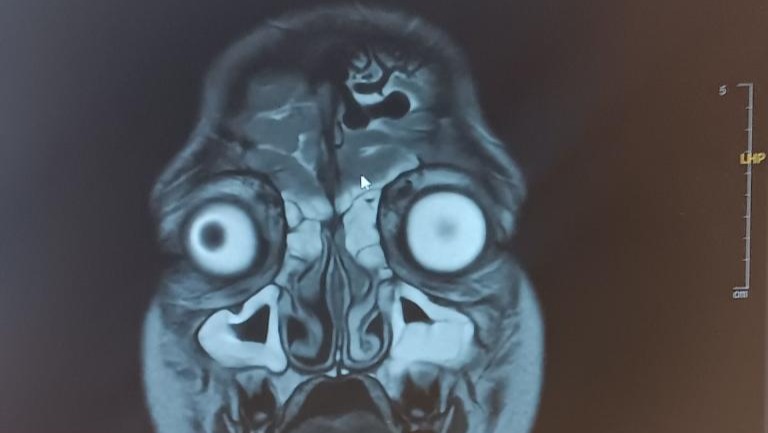

We were transported to another hospital where she received another head CT scan and the doctors explained it was serious and we needed to get an MRI. The results showed that not only does she have Chronic Sinusitis. She also has "Arteriovenous Malformation", which is an abnormal tangle of blood vessels that causes irregular connections between arteries and veins in the brain. Her blood vessels are enlarged. This could lead to rupture and her brain could bleed, it could also lead to paralysis and seizures. We are asking for support to get her back and forth to the neurosurgeon in Utah, and also help with the medical costs that come with this diagnosis. Our daughter needs treatment / surgery. Anything helps and we appreciate your support!